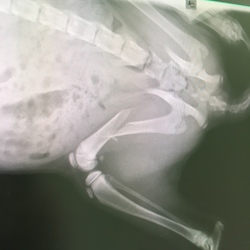

ルーシー骨折!

ルーシーさん骨折。目黒動物病院さんから小滝橋動物病院 目白通り高度医療センターにて手術。

5/18の夜発覚、5/19に初見病院に朝イチ診察、5/20上記病院に入院、5/21手術、5/28退院予定。